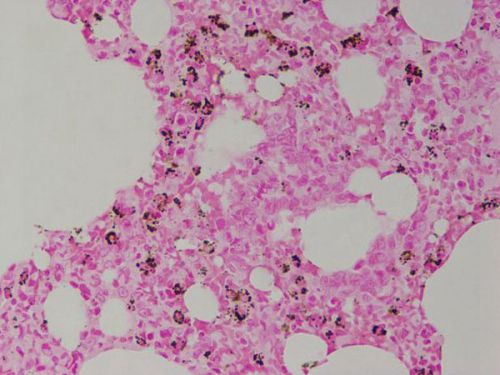

紅氨酸銅染色-大鼠肺

銅鹽沉積處呈深綠黑色,細胞核呈紅色。